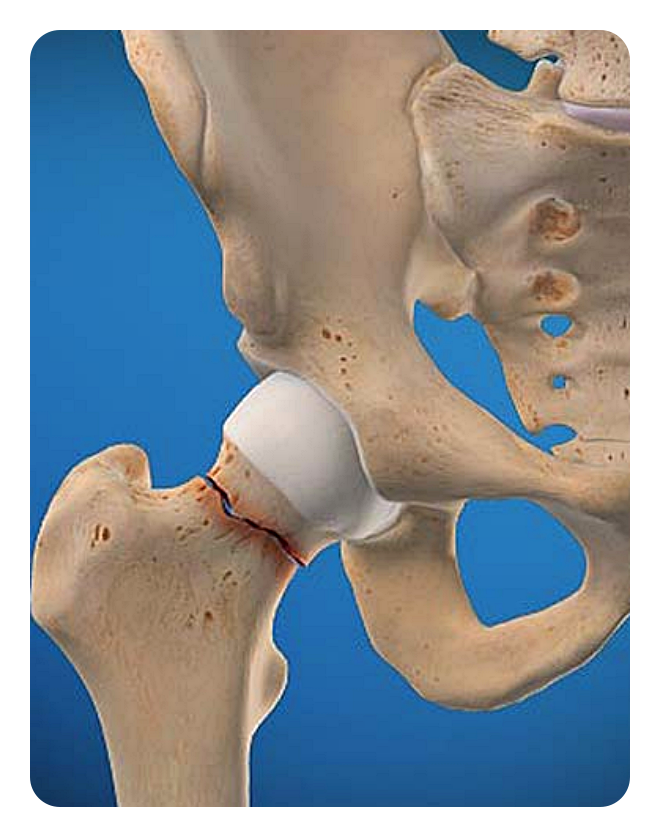

골절 고정술: 이 수술은 골절된 뼈를 원래 위치로 돌려놓고 고정하는 것으로, 골절된 부위가 제대로 회복되도록 돕습니다. 외부고정과 내부고정으로 나뉘어집니다.

또한, 관절의 손상이나 변형으로 인해 움직임이 제한된 분들도 인공관절 수술이 필요할 수 있습니다. 예를 들어, 고관절의 변형이 심해 걷거나 일어서는 것이 힘든 경우가 그렇습니다.

이런 경우, 고관절 수술이나 고관절 인공관절수술을 고려할 수 있습니다. 이러한 수술은 손상된 고관절을 대체하는 것으로, 통증을 줄이고 움직임을 회복하는 데에 효과적입니다. 그러나 이러한 수술은 높은 난이도와 부작용을 동반할 수 있으므로, 신중한 판단이 필요합니다.